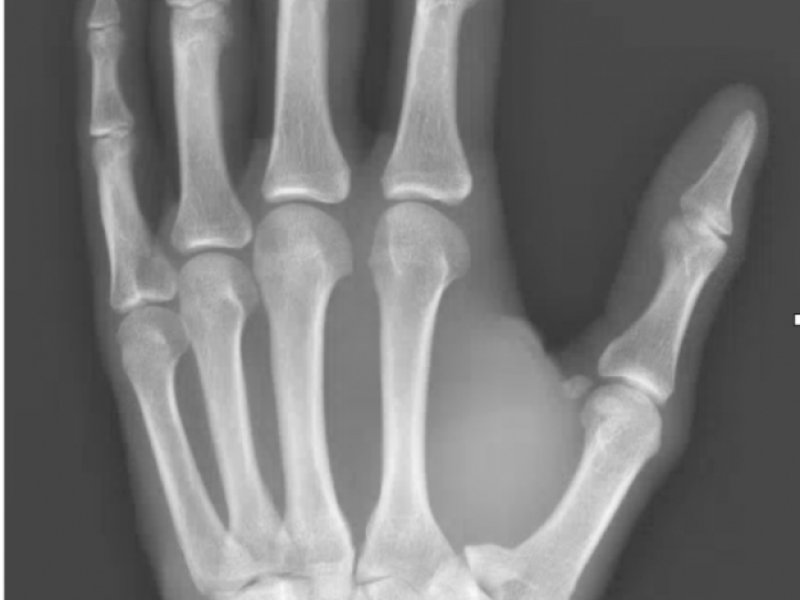

What's the Diagnosis? By Dr. Chris Smith

A 31 yo male presents with left thumb pain after a dirt bike